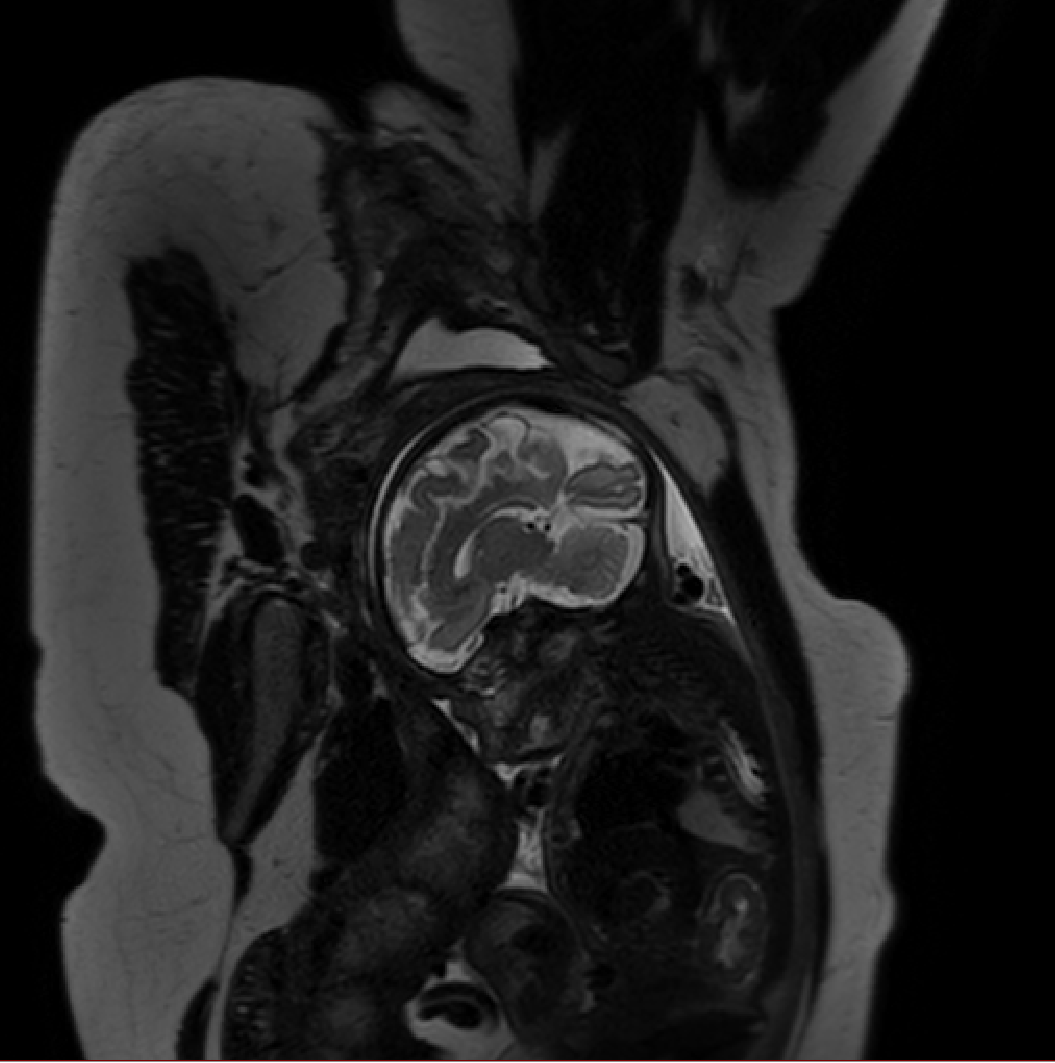

Table 1 lists average of quantitative evaluation results of these experiments and Figure 2 shows results obtained from each image. Figure 3 shows examples of the obtained segmentations.

Refer to caption

Figure 3: Example of ICV segmentations in images acquired in axial (left), coronal (middle) and sagittal (right) planes. Top row: A slice from T2-weigted image; Second row: Automatic segmentations obtained using 7 training images from the representative imaging planes; Third row: Automatic segmentations obtained using all 21 training images from all 3 image orientations; Bottom row: Manual segmentation.